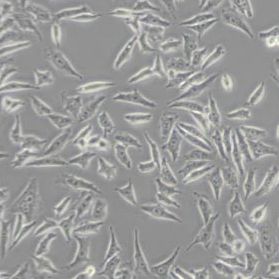

细胞中文名称:NCI-H358人非小细胞肺癌细胞(带STR鉴定)

| 细胞形态 | 上皮细胞样 |

| 背景描述 | NCI-H358细胞是于1981年从一位开始化疗之前的患者的肿瘤组织中分离得到的。超微结构研究表明,NCI-H358细胞的细胞质中有Clara细胞的特征结构,NCI-H358细胞表达主要的肺表面结合蛋白SP-A和RNA,不表达SP-B和SP-C;NCI-H358细胞在软琼脂中的克隆形成效率为0.83%。 |